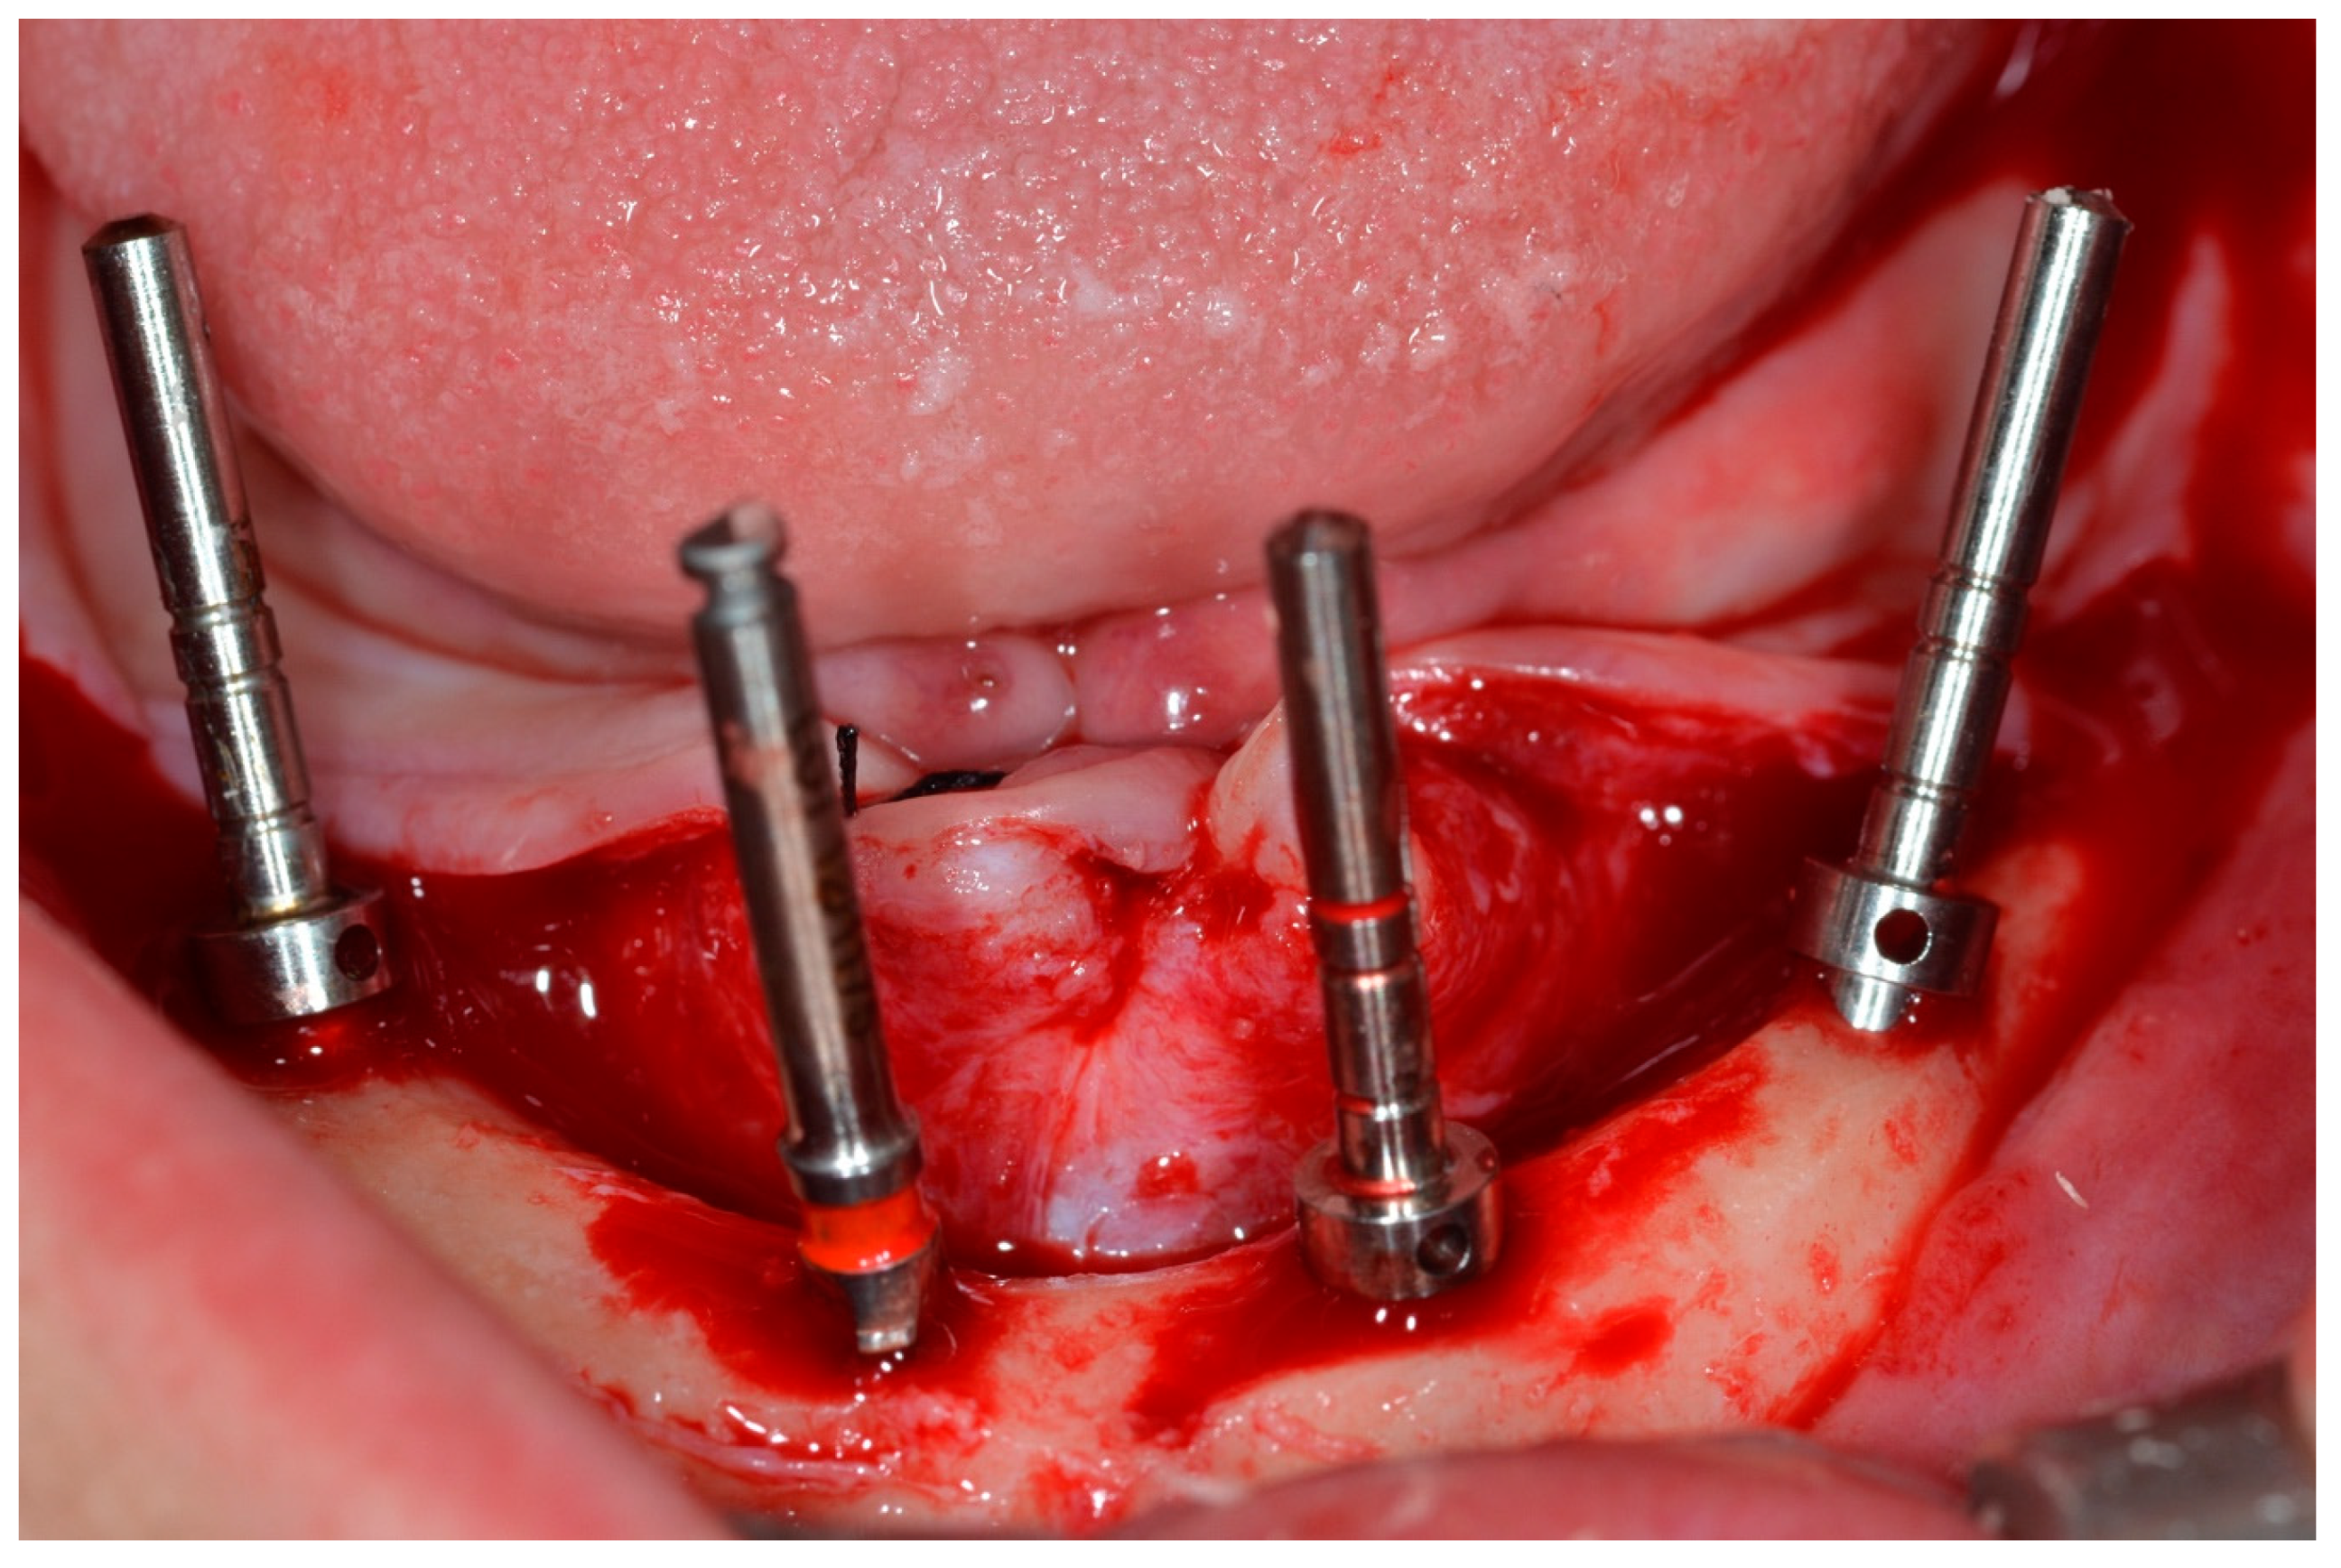

The drilling sequence for implant installation was performed according to the instructions of the implant manufacturer (Dérig, São Paulo, SP, Brazil), according to the All-on-Four protocol (Figure 4) [19,20,21].

Figure 4.

View of the mandible with parallel pins to check implant positions for the All-on-Four concept.